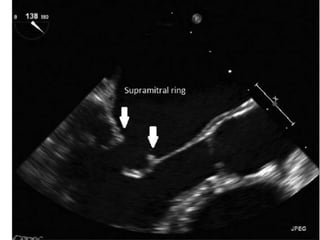

Supravalvular mitral ring

Mitral Stenosis etiology 1.Rheumatic: most common cause 2. Severe mitral annular calcification (MAC) 3. Congenital Parachute mitral valve: single papillary muscle to which chordae to both leaflets attach;results in mitral stenosis or mitral regurgitation Supravalvular mitral ring 4. Systemic diseases: can cause valvular fibrosis Carcinoid SLE RA Healed endocarditis